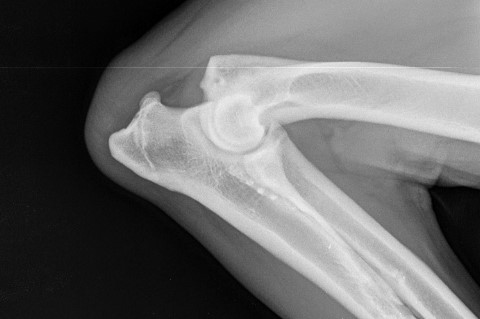

Werden instabile Gelenke nicht stabilisiert, entstehen Arthrosen, die dauerhaft zu Schmerzen und Leiden führen. Neben der Versorgung von Luxationen und Bänderrissen, wie z. B. Kreuzband-Operationen am Knie, operieren wir auch eine Vielzahl von Frakturen.

Die Stabilisierung eines Kreuzbandrisses erfolgt bei uns durch verschiedene chirurgische Verfahren (TPLO, TR, TTA). Die Auswahl der für Ihr Tier am geeignetsten OP-Methode wird jeweils ausführlich mit Ihnen besprochen.